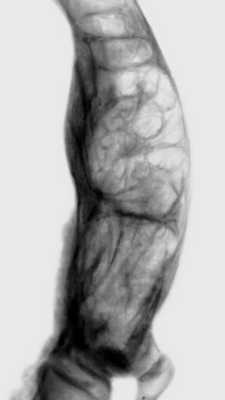

Диагноз устанавливают преимущественно на основании данных рентгенологического исследования. Ранние этапы болезни рентгенологически характеризуются изменениями внутренней архитектоники кости, затем к ним присоединяются утолщение и деформация кости. Наиболее типична для П. б. видимая на снимках груботрабекулярная перестройка костной ткани. Костные перекладины утолщаются, группируются в пучки, вследствие чего вся структура кости приобретает грубый вид, ячейки между костными перекладинами становятся крупными, неправильной формы (рис. 1), костные перекладины в основном сохраняют свою функциональную направленность. В процесс перестройки вовлекается и корковое вещество, которое приобретает волокнистый вид; в дальнейшем граница между корковым и губчатым веществом теряется, кость на уровне поражения утолщается, деформируется. Целость контуров кости всегда сохраняется. Перестраивающиеся длинные трубчатые кости постепенно искривляются (рис. 2), с выпуклой стороны нередко развиваются зоны патологической функциональной перестройки — Лоозера зоны.

Рентгенограмма дистального конца деформированной левой бедренной кости при болезни Педжета">

Рис. 1. Рентгенограмма левого тазобедренного сустава больного с болезнью Педжета: структура межвертельной области бедренной кости имеет грубый вид, ячейки (указаны стрелками) между костными перекладинами крупные, неправильной формы.